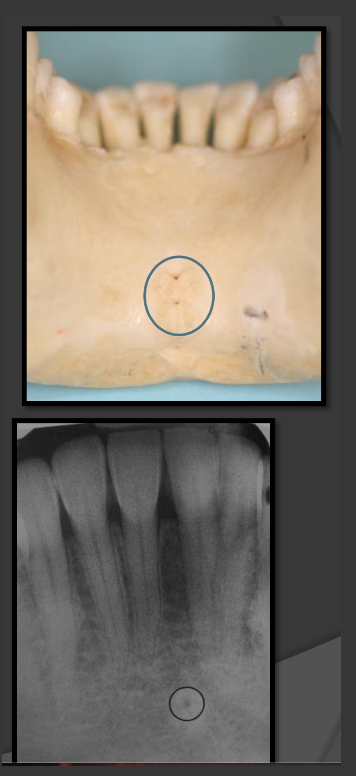

How does the genial tubercles/mental spines present in a radiograph?

Presents as a ring shaped radio opacity (white donut). Sits below the centrals on the mandible. It is the white portion. The radiolucent dot is a different structure

How does the lingual foramen present in a radiograph?

Presents as a tiny radiolucent dot below the mandibular centrals. Looks like a white donut because it is overlapping with the genial tubercle.